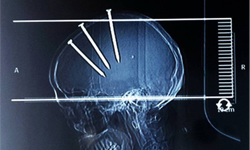

一位69歲中國福建男子前往就醫,X光照頭部發現驚人事實:他的腦袋卡進3根10公分長釘,穿透頭皮和頭骨,深入大腦組織!他非但奇蹟似地沒死,還意識清晰地謝絕院方報警處理,聲稱是自己所為。經由手術取出釘子之後3個月的療養期,醫師相信老人已完全復原,日前獲准出院。

即使他堅稱3根釘子是自己打進大腦的,基於傷勢嚴重性,醫師懷疑有人用這種殘忍行徑傷害他。幸運的是,這起事故沒有造成任何死亡,但也並未驚動警方展開調查。

手術取出3根長釘,復原狀況良好。